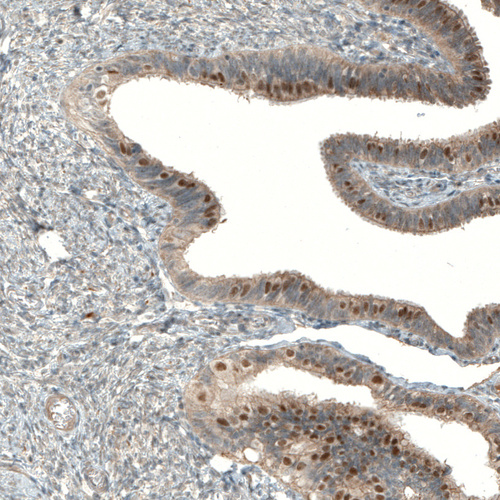

Immunohistochemical staining of human fallopian tube shows strong nuclear positivity in glandular cells.